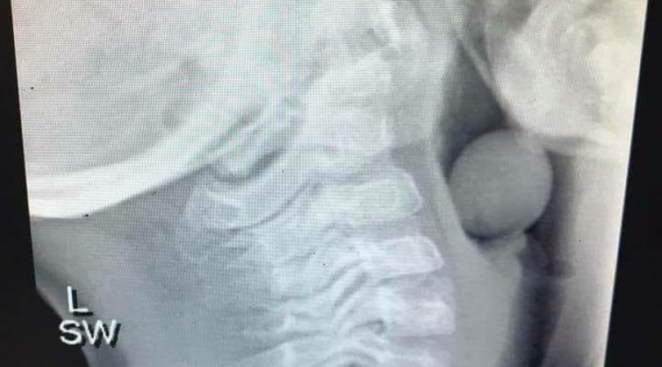

• Terrifying X-Ray Shows Why Toddlers Should Never Eat Grapes Without Supervision

Terrifying X-Ray Shows Why Toddlers Should Never Eat Grapes Without Supervision